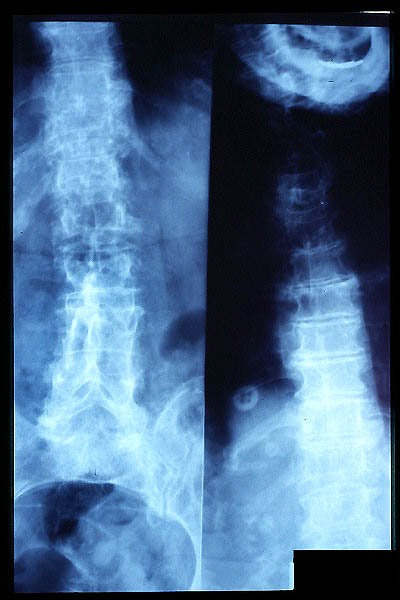

Escoliosis, artrosis, aplastamiento...

Escoliosis. Espondilolistesis.